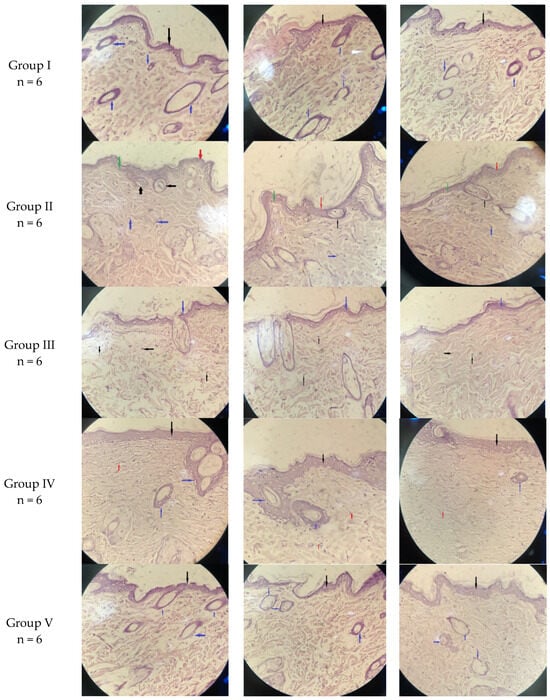

2.3. Histological Examination

3.4.8. Histopathological Analysis